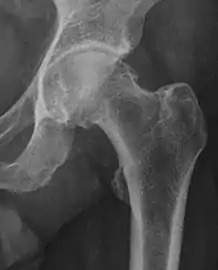

Projectional radiography ("X-ray")is often considered first line for FAI.[10] Anterior-posterior pelvis and a lateral image of the hip in question should be attained.[10] A 45-degree Dunn view is also recommended.[10][19]

| Femoral head-neck offset | ![]() |

Offset of the femoral head with regard to most prominent aspect of the femora neck | >10 mm |

| Offset percentage | Femoral head-neck offset related to femoral head diameter | >0.18

| |